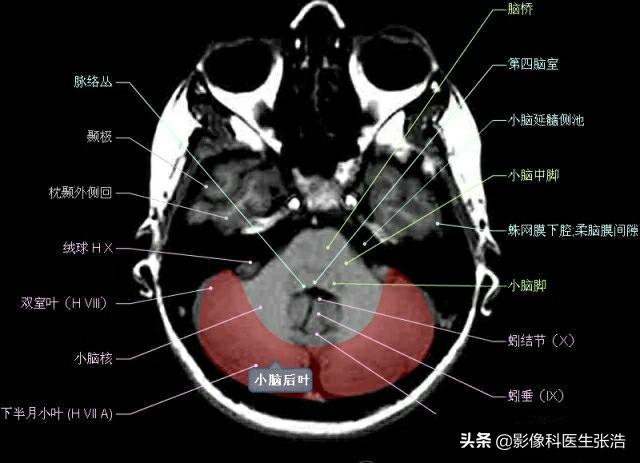

核磁共振(MRI)是一種利用磁場和射頻脈沖來生成身體內(nèi)部結構的詳細圖像的非侵入性檢查技術,頭部核磁共振主要用于檢查腦部疾病、神經(jīng)系統(tǒng)問題以及血管狀況等,這項檢查對于疾病的早期發(fā)現(xiàn)和治療具有非常重要的意義。